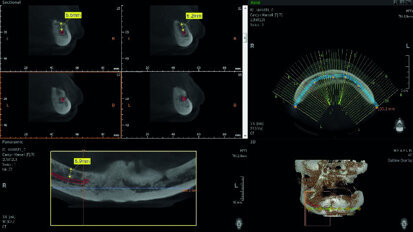

Meeting users’ needs: Dentsply Sirona releases Sidexis 4 V 4.3 and updates Orthophos SL

Dentsply Sirona has updated two imaging solutions: the imaging software Sidexis 4 and the software of the extraoral flagship, Orthophos SL. Dental practices...